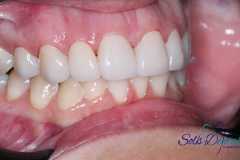

Paciente femenina, 19 años, con agenesia dental (ausencia de piezas de nacimiento), se realiza colocación de 2 implantes en piezas laterales, confección de provisionales y se esperan 4 meses para la colocación de piezas permanentes sobre implantes.